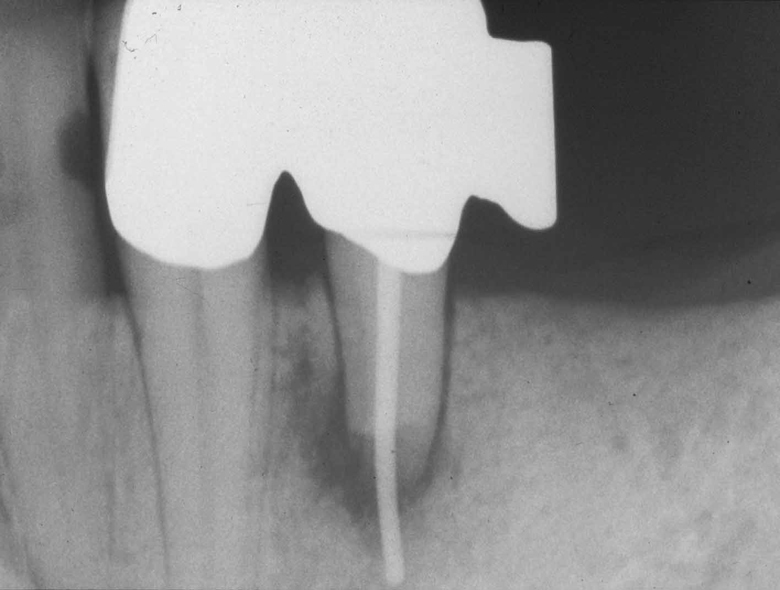

Unterer erster Prämolar im Zustand nach Wurzelspitzenresektion und Versorgung mit einem transdentalen Wurzelstift als transparentes Präparat.

Extraktionsgrund: Chronische apikale Parodontitis

Präparation und Reinigung haben sich auf eine Vorbohrung zum Einsetzen

des Wurzelstifts in den Bereich des bukkalen Wurzelkanals beschränkt.

In allen Anteilen der Pulpahohlräume (im gemeinsamen koronalen

Verlauf, im Verlauf des separaten und durchbohrten bukkalen Kanals und im

nicht entdeckten lingualen Wurzelkanal) befinden sich dunkle Massen, von

denen aus pigmenthaltige Substanzen tief in das Dentin diffundiert sind.